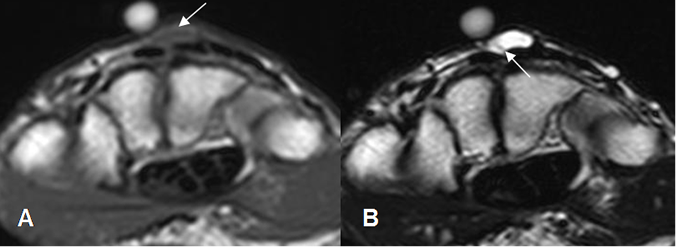

En la RM son hipointensos, isointensos o hiperintensos con relación al músculo en T1, dependiendo de su contenido. Hiperintensos uniformes en T2, con un fino borde hipointenso, que puede presentar septos, los cuales realzan con el contraste. (18). (Fig 107 y 108).

Fig 107. Ganglión quístico.

A: RM axial en T1 y B: RM axial en T2. Lesión isointensa en T1 e hiperintensa en T2 en el dorso del carpo, por ganglión quístico. Se observa septo delgado en T2. (Flecha).